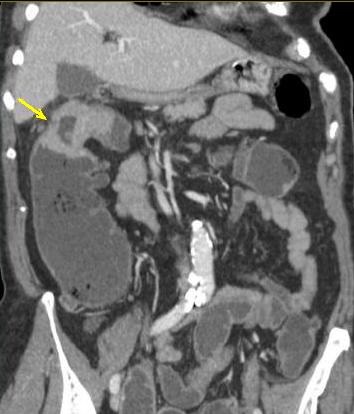

Coloscanner a

l'eau : C'est la TDM avec une opacification du

colon a l'eau tiede ( comme une lavement baryte ) a l'aide

une sonde rectale . L'exploration et les exposes represence

apres distension colique a l'eau tiede avec injection de

contrast iode hydrosoluble

par voie intraveineuse :

Image d'une polyp du colon (

fleche rouge ) . Colos scanner a eau en coupe axiale

. Cette technique peu elimine des polyps de plus de

7mm |

Aspect de même polyp

en vue par technique Coloscopie virtuelle |